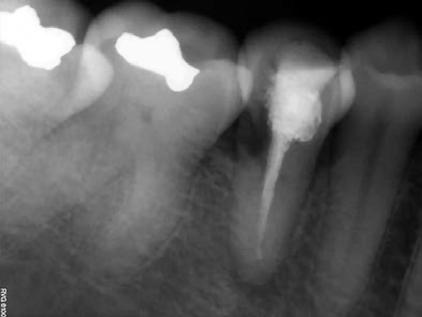

1. ábra: A 15-ös foggyökér meziális felszíne mellett látható radiolucens elváltozás, illetve a felvételen látható a korábban behelyezett gyökértömés, a parapulpális csap segítségével elhorgonyzott csonkfelépítés és a fogat borító cirkonkorona. –2. ábra: A saggitalis irányú CBCT-metszeten jól megfigyelhető az állcsontgerincet elérő radiolucens elváltozás. – 3. ábra: Az axiális irányú CBCT-metszeten egyértelműen látható a kezeletlen palatinális gyökércsatorna, valamint a radiolucens elváltozás mezio-disztális kiterjedése is jól megítélhető. – 4. ábra: A palatinális gyökércsatorna szelektív endodonciai kezelése során először gyógyszeres zárás került behelyezésre. – 5. ábra: A gyógyszeres zárás során alkalmazott kalcium-hidroxid alapú paszta a szulkuszon keresztül a szájüregbe extrudálódott. – 6. ábra: A gyökértömő anyag a középső és apikális gyökéri harmad határán lévő laterális csatornán keresztül a periapikális térbe extrudálódott. 7. ábra: A kezelések befejezését követően 4 évvel készült röntgenfelvételen jól látható a csontállomány gyógyulása és a fiziológiás gyökérhártyarés újbóli kialakulása. –8. ábra: A peroperatív CBCT-felvétel alapján készített koronális irányú metszeten jól látható a gyökércsúcs körül lévő periapikális felritkulás. – 9. ábra: A kezelések befejezése után 4 évvel készített CBCT-felvételen a gyulladásos lézió teljes megszűnése észlelhető.

A CBCT-készülékek endodonciai alkalmazásának talán az az egyik legnagyobb előnye, hogy így olyan anatómiai struktúrák is láthatóvá válnak, amelyeket egyébként nem tudnánk detektálni panoráma, cephalo, vagy periapicalis felvételek segítségével. Mivel a CBCT-felvételek kiértékelése számítógép segítségével történik, így a felvételek vizsgálata során lehetőségünk van az adott területet több nézőpontból és több síkban is megvizsgálni. 2015 októberében egy korábban a rendelőnkben kezelt 55 éves férfi páciens azzal a céllal kereste fel ismét a rendelőnket, hogy másodvéleményt kérjen egy jobb felső kvadránsban található fogával kapcsolatban. Egy másik rendelőben történő vizsgálat során a panaszos fog törését vélelmezték és a fog eltávolítását javasolták, illetve arról is beszámolt, hogy az elmúlt hét során ezen a területen egy puha duzzanat is kialakult. A klinikai vizsgálat során a jobb felső első és második kisőrlő között (14–15) egy fluktuáló duzzanatot észleltünk az áthajlásban. Az 15-ös fog mesialis oldalán 12 mm mély tasakot szondáztunk. A páciens által hozott periapicalis felvételen a 15-ös fog gyökércsúcsának mesialis részén egy nagy kiterjedésű radiolucens elváltozás volt észlelhető (1. ábra). A saggitális síkban vizsgált CBCT-felvételen (Carestream CS 9000, Carestream Dental) a lézió valódi kiterjedése is láthatóvá vált (2. ábra). A megelőző endodonciai kezelések során csupán a bukkális csatorna került detektálásra és gyökértöméssel való ellátásra. Az axiális irányú CBCT-szeleteken egyértelműen látható volt az ellátatlan palatinális gyökércsatorna (3. ábra)

Először kalcium-hidroxid alapú ideglenes gyógyszeres zárás került a palatinális csatornába (UltraCal XS, Ultradent Products; 4–5. ábra), amelyet 6 hét után a végleges gyökértömés elkészítése előtt eltávolítottunk. A gyökértömés elkészítése során meleg vertikális kondenzációs technikát alkalmaztunk. Radiológiai felvételen megfigyelhető volt, hogy a gyökértömő anyag egy laterális csatornán keresztül kis mennyiségben a periapicalis térbe extrudálódott (6. ábra). A 4 évvel később készített kontrollfelvételeken a lézió gyógyulása volt megfigyelhető (7–9. ábra). A vizsgálati eredmények és a kezelés kimenetele egyértelműen igazolta, hogy nem gyökérfraktúrával álltunk szemben, tehát a kezdeti diagnózis tévesnek bizonyult. Ez is azt erősíti, hogy korlátozott mennyiségben rendelkezésre álló adatok alapján nem lehet pontos diagnózist felállítani. Manapság szinte elengedhetetlen a CBCT-felvételek endodonciai beavatkozások során történő használata, feltéve, ha ezek elkészítése során az ALARA elv (as low as reasonably achievable) betartásra kerül.